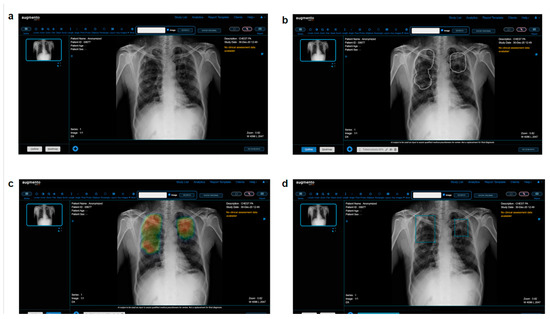

2.3. AI Model

- AUGMENTO. Available online: https://www.deeptek.ai/augmento (accessed on 6 December 2022).